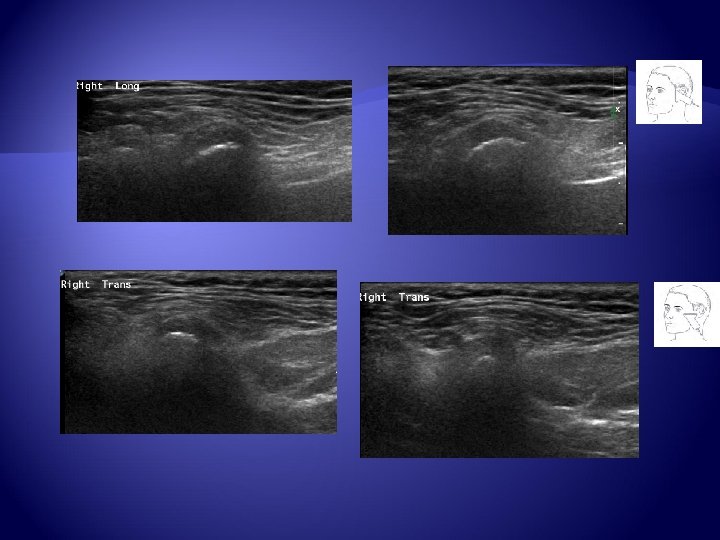

Ultrazvukové vyšetření Lineární vysokofrekvenční sonda ( 12 -17 MHz) Longitudinální a transverzální rovina Povrch hlavičky kondylu Výpotek Poloha disku – hypo-izoechogenní struktura, norma – střední část nepřesahuje anteriosuperiorní kompartment hlavičky Real time při otevírání úst